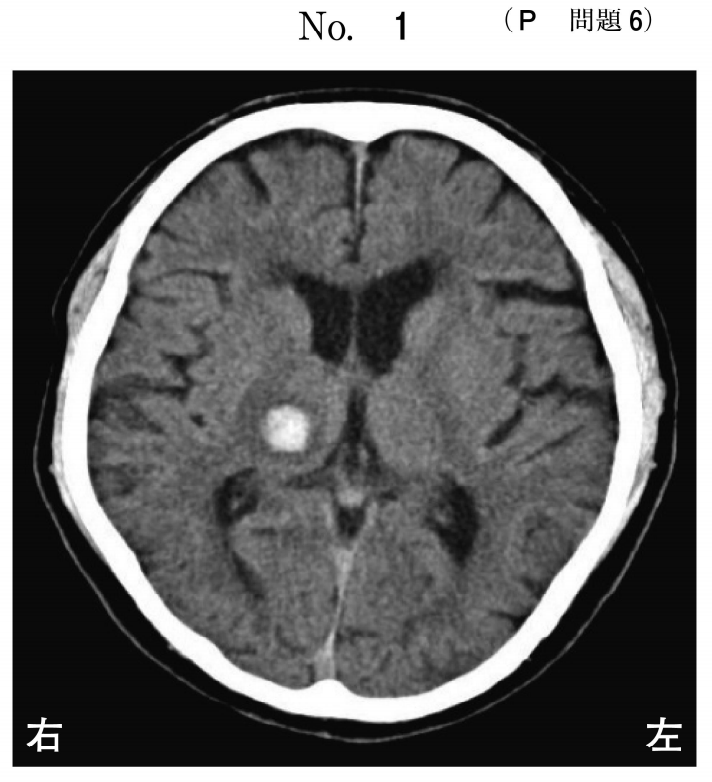

トップ 医療・介護・福祉に関する資格 理学療法士 平成30年度 第53回 過去問(2018年度) 問6 全部で95問 挑戦中 午後 問題 脳出血後の頭部CT(別冊No.1)を別に示す。最も生じゃすい症状はどれか。 (1) 系列的な動作が順番通りにできない。 脳出血発症前のことが思い出せない。 左からの刺激に反応しない。 左手の感覚が脱失する。 人の顔が区別できない。 次の問題へ